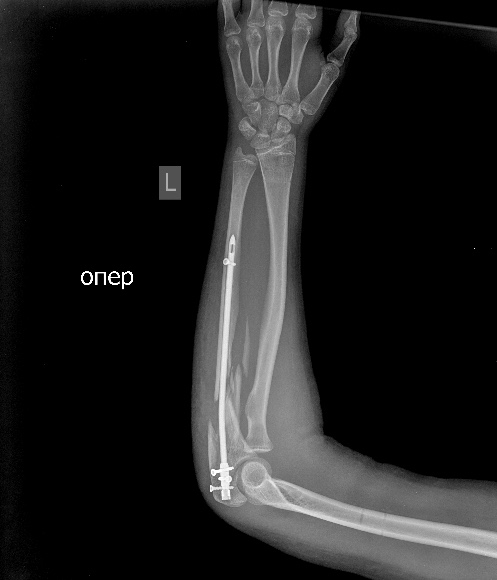

псевдоартроз локтевой с застарелым вывихом радиоульнарного сочленения |

Возможно, и поменяет. Позволит оценить некоторые аспекты. Характер псевдоартроза, смещения и т.д. Вообще, как-то странновато - ложный сустав, два вывиха на одном сегменте и снимок в одной проекции?! Поскольку второй проекции дождаться не удалось, предложу следующий план решения проблемы: Удаление пластины, остеосинтез аппаратом, постепенная дистракция, чрезочаговая репозиция спицами с упорами оставшихся смещений. Дёшево и эффективно. Вторая проекция помогла бы детализировать некоторые моменты. Ниже очень похожий случай, пациент оперирован через 8 месяцев после травмы.

Мы бы удалили пластину. Аппаратом постепенно восстановили бы взаимоотношения. И заштифтовали бы локтевую кость, смоделировав стержень, чтобы он был напряжен в противоположную сторону тому, как сейчас выглядит локтевая кость, т.е. вогнутой стороной в сторону межкостного промежутка. Чтобы лучевая кость удерживалась натяжением межкостной мембраны. Пример в приложении. Тут был более свежий случай, поэтому вправилось одномоментно.